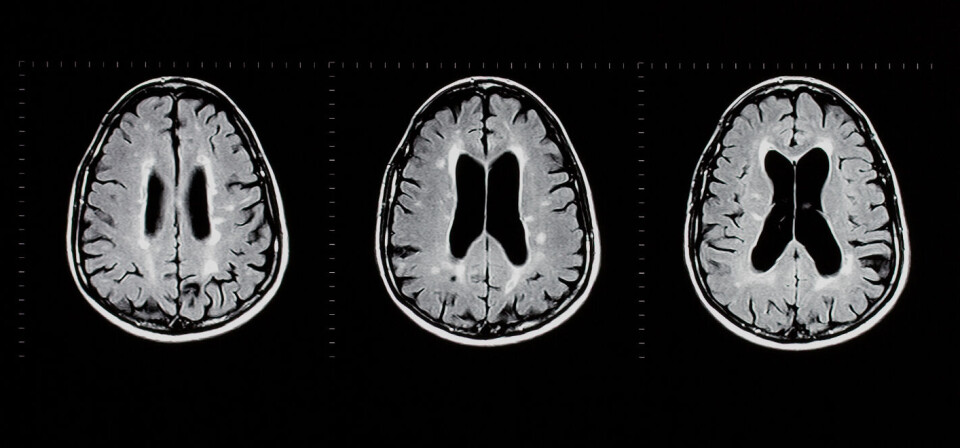

Det tyske legemiddelselskapet Merck har fått grønt lys fra EU-kommisjonen til å markedsføre legemiddelet kladribin (Mavenclad) på det europeiske markedet. Medikamentet er godkjent til behandling av attakkpreget multippel sklerose, kunngjorde Merck fredag. EU-godkjennelsen er basert på data om mer enn 2700 pasienter, blant annet fra tre fase 3-studier.